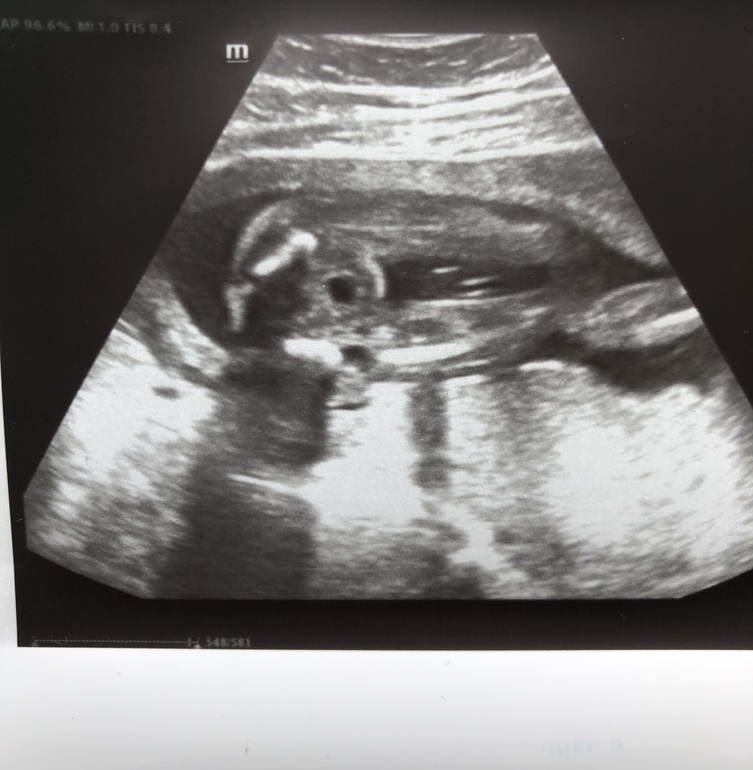

и фото в 20 недель:

Даа,это девочка :) и краевое предлежание плаценты :(

Результаты: УЗИ, КТГ, доплера, скринингаСегодня 20+1 недель,были на втором скрининге,с 16й недели ничего не выросло там 😅Длинноногая красотка сидит,как партизан :) пытается все спрятать,еле смогли рассмотреть все что надо.

Из не очень хороших новостей:

Краевое предлежание плаценты.С сыном тоже была низко,но по-моему к этому сроку начала подниматься 😔 Никак нельзя помочь этому процессу?И если на таком сроке не поднялась,есть шанс,что ещё поднимется?